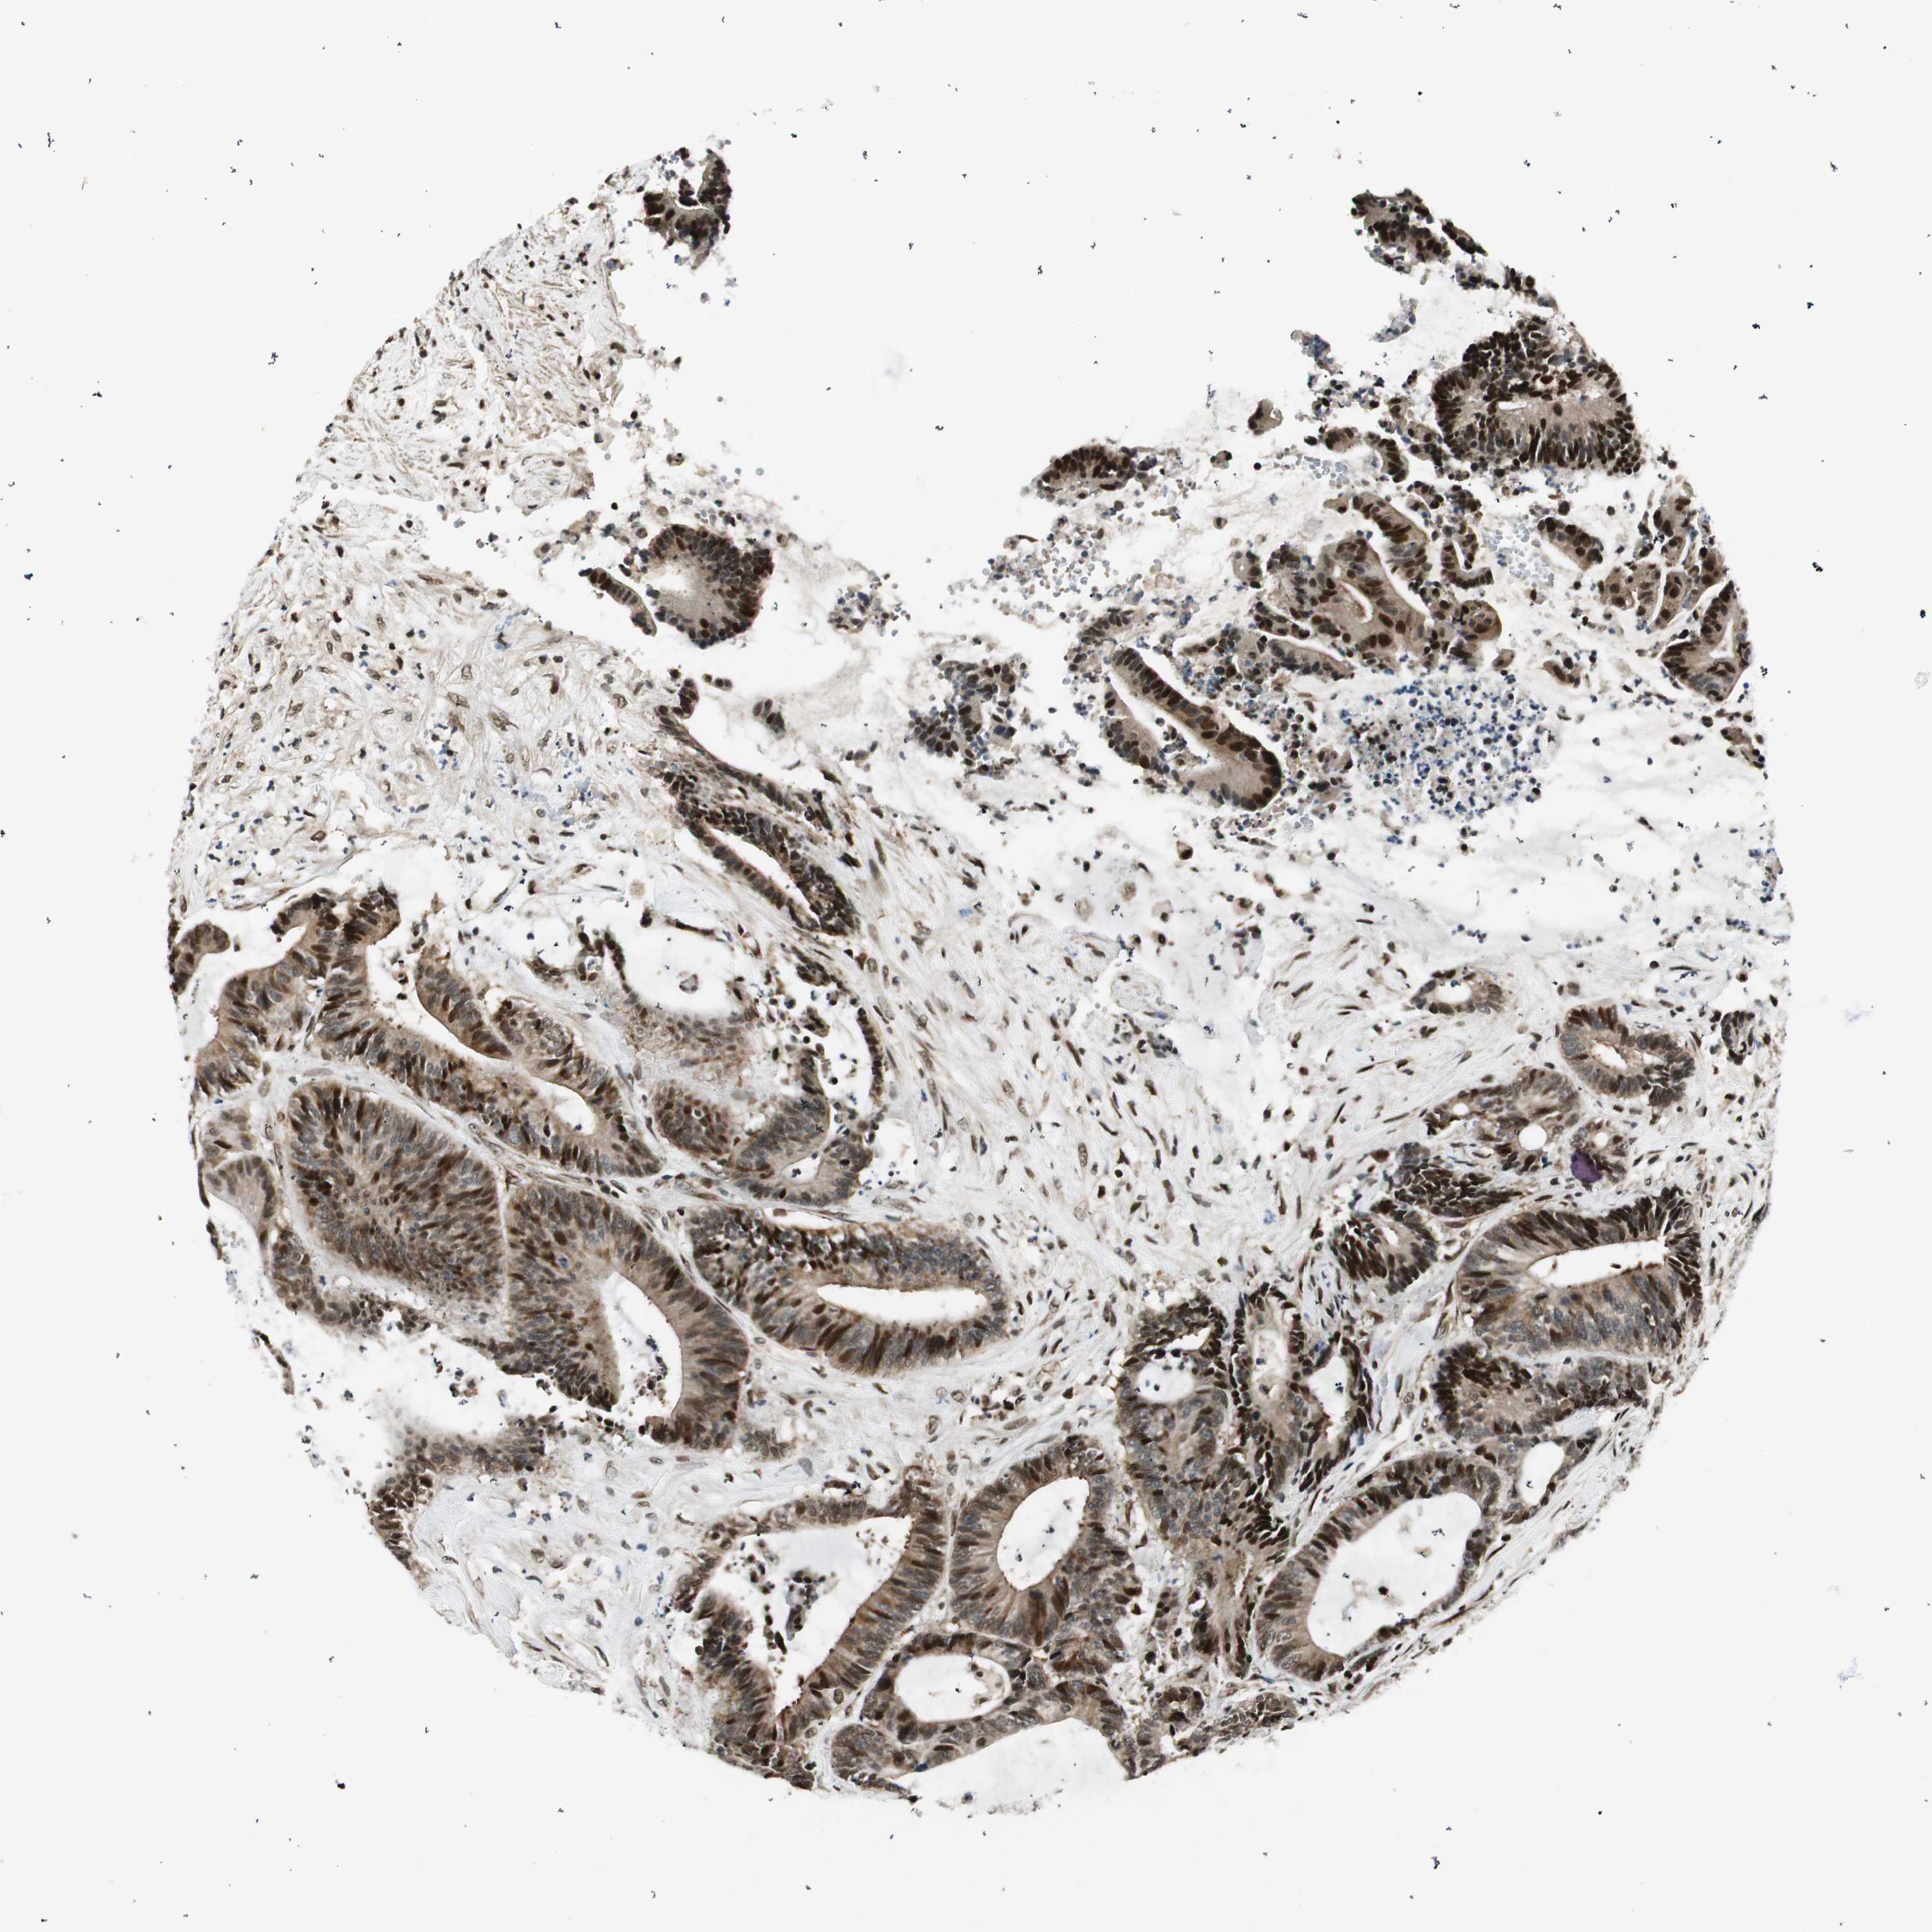

CANCER COLORECTAL CANCER Show tissue menu

Colorectal cancer

Human cancer

Colon adenocarcinoma